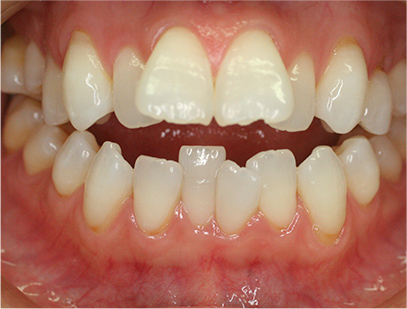

前歯が咬み合っていなく反対咬合の症例

上下の前歯が咬んでない事を主訴として来院されました。通常どおり検査を行い「前歯部に開咬を伴う反対咬合」と診断されました。

治療前

• 正面

治療前の写真と治療後の写真を比べると口元が治療前は下唇が出ていて、鼻の下が凹んでいました。上顎の前歯のデコボコも綺麗に並びました。また、上下の前歯は開咬が治りしっかりと咬み合ってます。

治療期間は患者様の協力が大変に良かったために2年半とさほど長くはありませんでした。

• 口元が綺麗になった事、上下の前歯が咬み合った事、八重歯が改善された事。